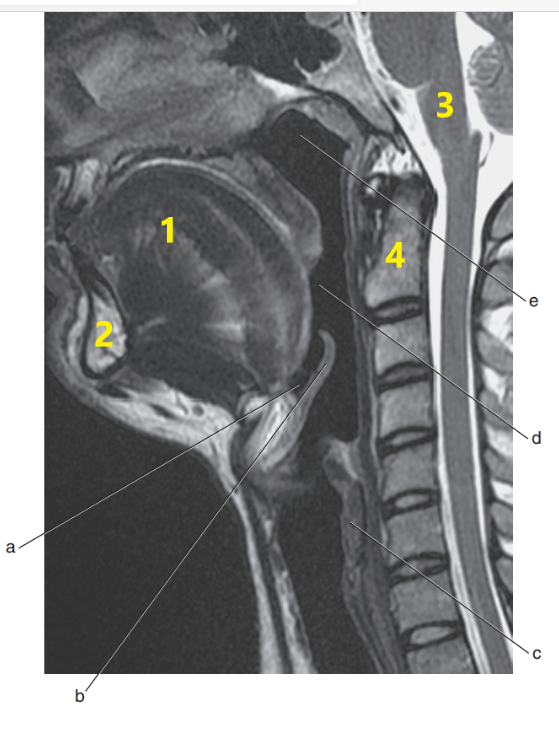

Nasopharynx

What is # 1 ?

Mandible

What is # 4 ?

C-1/C-2

Tongue

Epiglottis

Soft palate

Cervical spine

What is # 3 ?

Brain stem